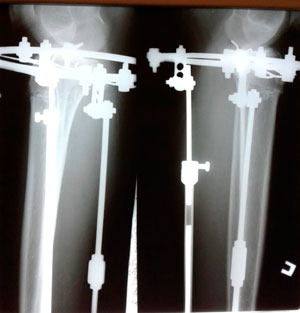

Исходник - 42 года.

Дата операции - 27.05.2020